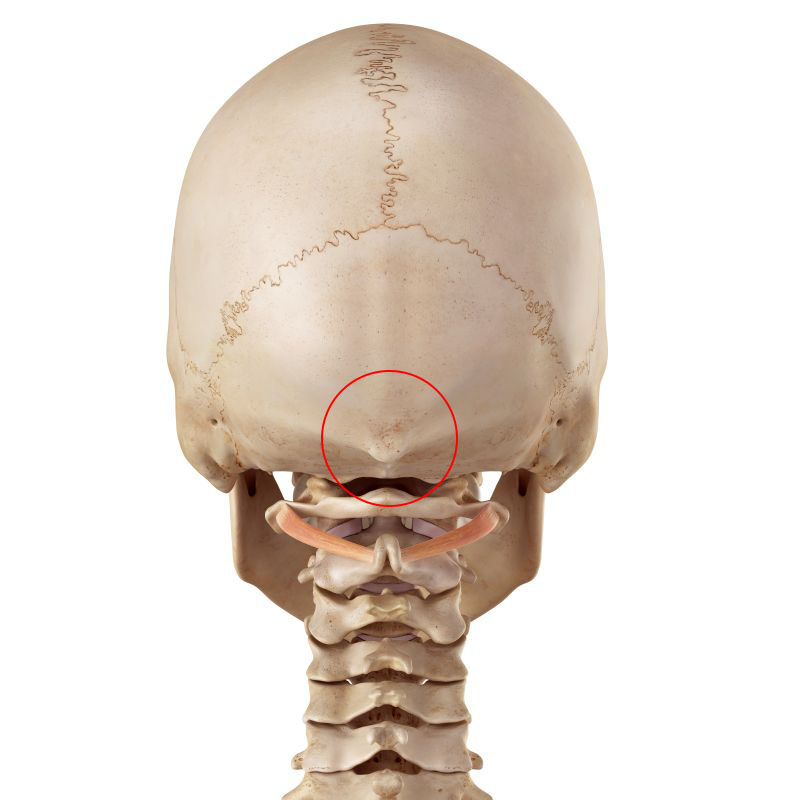

Az inion (protuberantia occipitalis externa) a nyakszirtcsont legkiállóbb része, ahonnan a tarkószalag és a trapézizom egyes rostjai erednek.

Az inion (bekarikázva)